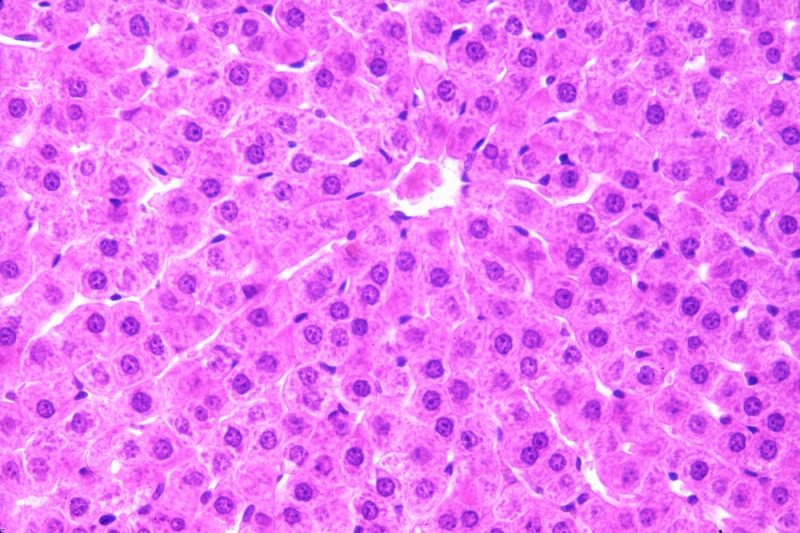

Hepatocitele: celulele cheie ale ficatului și rolul lor în funcționarea acestuia

Ficatul, cel mai mare organ intern, susține organismul în fiecare zi, asigurând procesarea nutrienților, filtrarea toxinelor și multe alte funcții...